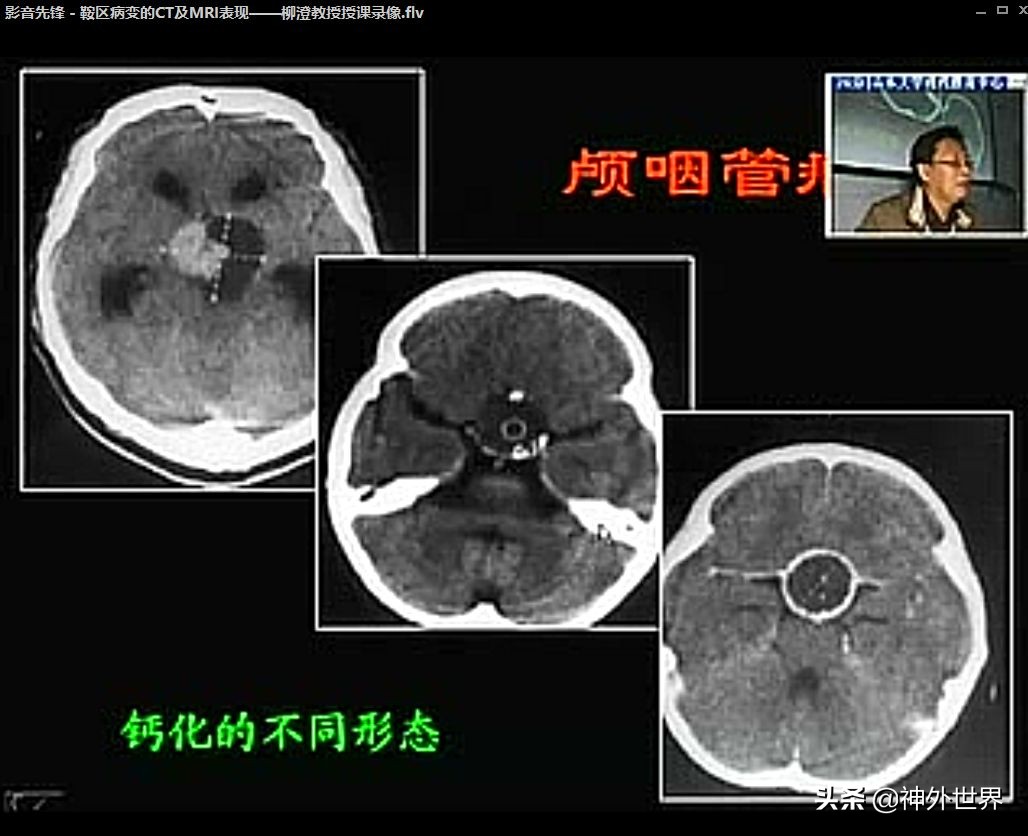

- 颅咽管瘤:鞍区钙化+囊变+实质结构是其主要特征。【Rathke囊发育退化不全,未完全闭合的颅咽管胚胎性鳞状细胞发展成颅咽管瘤。这些残存的颅咽管位于垂体前叶和垂体柄,因此儿童颅咽管瘤可起源于鞍内的垂体前叶(鞍内型)和鞍上的垂体柄(鞍上型)】。

《鞍区病变的CT 及MRI表现》——柳橙教授授课录像